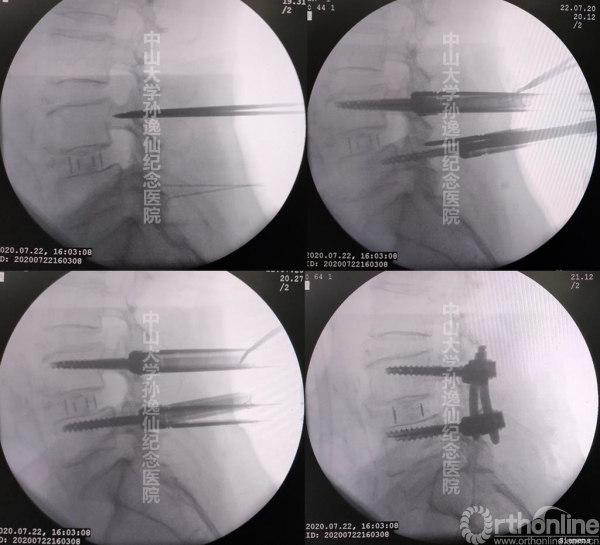

图4:侧卧位经皮椎弓根螺钉置钉及加压操作

置钉前先将患者从折腰位恢复至标准侧卧位,C臂定位L4-5双侧椎弓根鱼眼进钉点体表透射位置并标记。先利用长针头定位椎弓根进钉点,透视确认位置正确后,在针头处纵向切开皮肤约2cm,用穿刺针按定位置入鱼眼处,C臂反复透视中缓慢进入椎体。穿刺针安全通过椎弓根后,取出针芯放入导丝,在导丝引导下先利用软组织扩张器逐层扩张并置入适当长度和直径的椎弓根螺钉。以相同步骤逐一置入4枚椎弓根螺钉,C臂透视确认椎弓根螺钉位置良好后,常规置入钛棒并加压旋紧。

图5:侧卧位经皮椎弓根螺钉置入

图6:侧卧位经皮椎弓根钉置入术中C臂透视